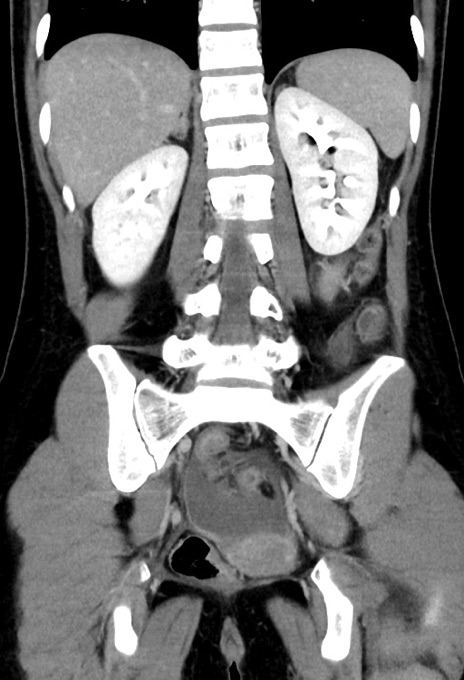

症例17(冠状断像)

【症例】20歳代女性

【主訴】嘔吐、下腹部痛

【現病歴】昨日夕食後に嘔吐し下腹部痛が出現。本日になっても嘔吐持続し改善しないため来院。

【身体所見】意識清明、BT 37.2℃、BP 108/67mmHg、腹部:平坦、やや硬、下腹部正中から右にかけて圧痛あり、反跳痛軽度あり、tapping pain(+)。

【データ】WBC 13600、CRP 14.94